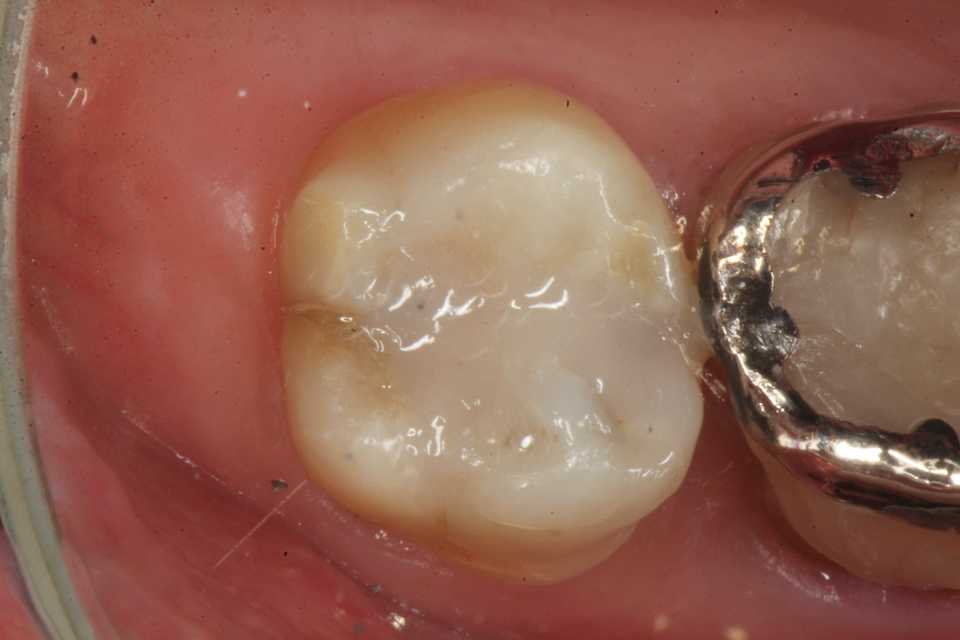

歯茎部カリエス(応力腐食割れ)0.2 2025.08.01

歯茎部カリエス(応力腐食割れ)0.1 2025.07.31

歯茎部カリエス(応力腐食割れ)0.0 2025.07.26